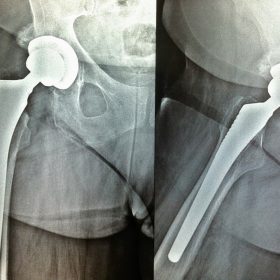

Σε αυτό το σημείο η Αρθροπλαστική Ισχίου αποτελεί μονόδρομο.

Παραδοσιακά οι αρθροπλαστικές ισχίου αποτελούνται από μια μεταλλική μπάλα – σφαίρα τοποθετημένη σε μια πλαστική κοιλότητα (κοτυλιαία πρόθεση).

Η πλαστική επιφάνεια στήριξης φθείρεται με την πάροδο του χρόνο, με ρυθμό μάλλον σχετιζόμενο με το επίπεδο δραστηριότητας του ατόμου. Αυτό έχει σαν επακόλουθο νεότεροι ασθενείς με μεγαλύτερο προσδόκιμο ζωής να έχουν αυξημένο ρίσκο αναγκαιότητας δεύτερης αρθροπλαστικής ισχίου (αναθεώρησης – Revision) επέμβαση που είναι πολυπλοκότερη και υπόκεινται σε υψηλότερο κίνδυνο επιπλοκών. Βάση των ανωτέρω, ιστορικά, η αρθροπλαστική ισχίου σπανίως εφαρμοζόταν σε ασθενείς κάτω των 60 ετών.

Χάρη στα νέα τεχνολογικά επιτεύγματα έχουν παραχθεί επιφάνειες στήριξης που ανταποκρίνονται σε μεγαλύτερα επίπεδα δραστηριότητας και αναμένεται να έχουν μεγαλύτερη διάρκεια ζωής. Αυτές οι καινούριες επιφάνειες στήριξης είναι συνήθως μέταλλο πάνω σε ειδικό σκληρότερο πλαστικό ή κεραμικό πάνω σε κεραμικό. Ως εκ τούτου, είναι τώρα πολύ πιο σύνηθες, νεότεροι ασθενείς να χειρουργούνται καθώς η πλειονότητα αυτών, που η αρθρίτιδα τους προκαλεί αφόρητους πόνους, επιλέγουν να έχουν ποιότητα ζωής από το να ζουν με τον πόνο.

Η αρθροπλαστική ισχίου αποτελεί μια αποτελεσματική επέμβαση αποκατάστασης και πρέπει να εφαρμόζεται μόνο όταν οι ασθενείς δεν είναι σε θέση να αντέξουν άλλο τον πόνο και την ανικανότητα και εφόσον τα πλεονεκτήματα καθώς και οι πιθανοί κίνδυνοι της μεθόδου έχουν εξηγηθεί πλήρως από το χειρουργό και έχουν κατανοηθεί από τον ασθενή.